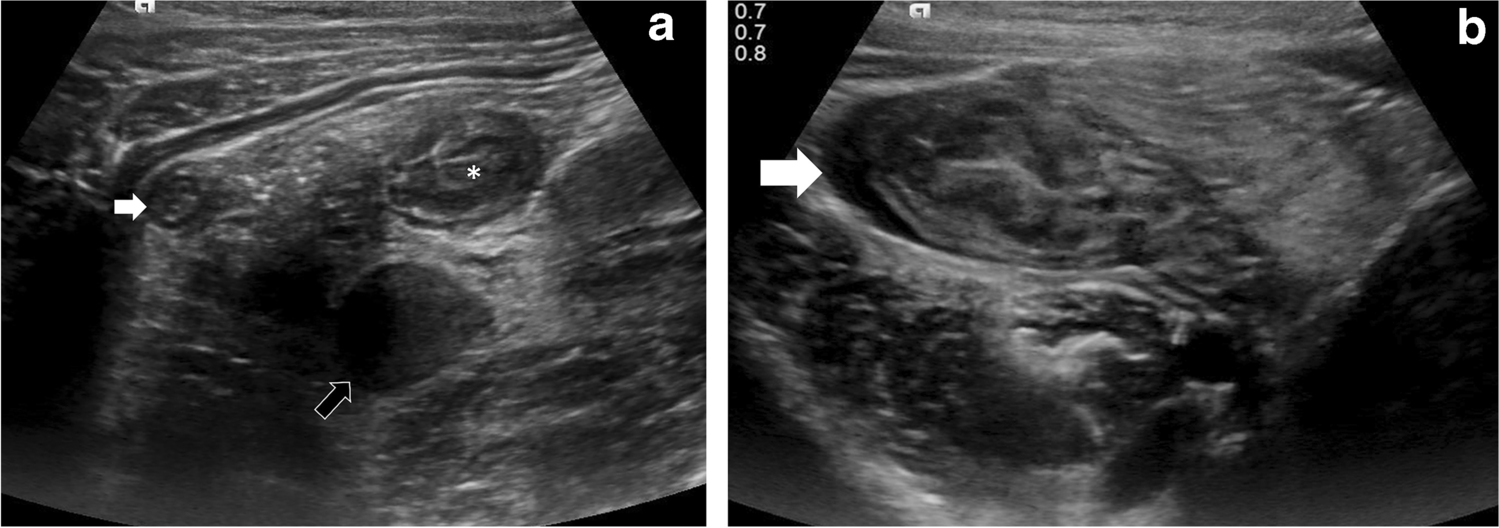

Fig. 3

Case 5: A 7-year-old girl presenting with a 3-day history of right iliac fossa pain. a Abdominal US transverse section at presentation shows diffuse right iliac fossa inflammation with free fluid and possible appendicitis. b, c CT scan (coronal post-contrast) next day confirms extensive right iliac fossa mesenteric inflammation with enlarged lymph nodes, free fluid, thickened appendix (6 mm, white arrow), with a small 3-mm appendicolith in the mid segment (black arrow) and thickened walls of distal ileum, cecum, proximal ascending colon and sigmoid colon. d MRI (T2-W coronal) on day 5 of admission shows similar findings with a small, localized collection in the peri-cecal region (*) with suspicion of a perforated appendix tip. This was followed up on US (not shown), which confirmed resolution of the collection and inflammatory changes after medical management. No surgical intervention was required

We had one complex case (patient 5, Fig. 3) who presented with a 3-day history of high fever, abdominal pain and vomiting. Initial US demonstrated caecal and ileal wall thickening, inflamed appendix (6-mm diameter), multiple enlarged lymph nodes (short-axis 15 mm), free fluid and mesenteric inflammation in the right iliac fossa. PIMS-TS was suggested based on US and clinical presentation, with laboratory tests supporting the diagnosis. CT scan was performed 24 h later, and the findings mirrored the US findings but also showed a small 3-mm appendicolith. MRI performed on day 5 demonstrated a pelvic collection adjacent to the appendix tip with possible appendix perforation. PIMS-TS medical management (IV immunoglobulins and IV methylprednisolone) with continuation of intravenous IV antibiotics led to resolution of inflammatory changes and collection on subsequent US. This was a rare case of appendix perforation secondary to PIMS-TS presenting in the latent phase. The presence of an appendicolith could have been responsible for early perforation in this case. A study of 388 patients with acute appendicitis has shown that appendiceal perforation is more common in the presence of an appendicolith (P<0.001) [35].

Another important observation in our study is evidence of appendiceal involvement in 7/23 (30%) cases, which is contrary to the current literature on PIMS-TS (Figs. 1, 2, 3 and 4). In a routine clinical setting, acute appendicitis (enlarged appendix ≥6 mm) is commonly associated with peri-appendiceal fat-stranding, focal cecal apical thickening (arrowhead sign), adenopathy, fluid in right paracolic gutter or appendicolith [27]. In our study, all cases with appendiceal thickening also had distal ileum (not limited to ileo-cecal junction) and cecum (circumferential wall thickening extending to involve the ascending colon in some cases) involvement, in addition to mesenteric inflammation, lymphadenopathy, and free fluid (Fig. 4).